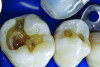

Figure 6. Amalgam is not usually bonded to the walls of the cavity preparation; thus, a space of several microns commonly exists between the restoration and the prepared surfaces. This leads to a potential for microbial invasion and secondary caries, as in this case of these defective amalgam restorations with recurrent decay.

Figure 6

Figure 7. The occlusal outline was extended only to include carious enamel, provide access to the carious dentin, and remove any residual amalgam staining.

Figure 7